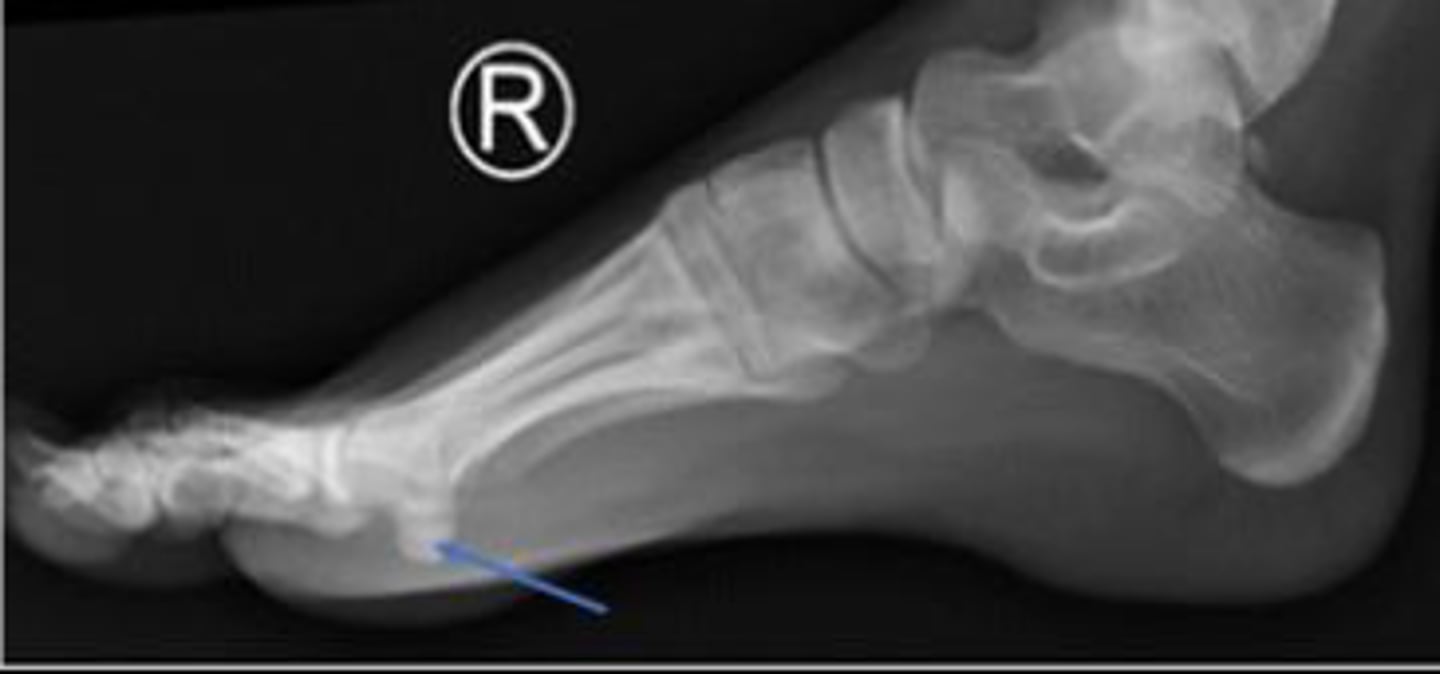

Right lateral foot

What is the name of the radiographic view?

Heel pad of the right foot

What are the arrows pointing to?

Head of the talus of the right foot

Calcaneus of the right foot

Navicular of the right foo

What is outlined?

Medial malleolus of the right foot

What is the arrow pointing to?

Heel pad measurement

What is the name of the assessment?

Females: average 19mm (maximum of 23mm)

Males: average 19mm (maximum of 25mm)

What is the normal range for the assessment?

Achille's tendon thickness

4-8mm

Yes

Is the assessment within normal limits?